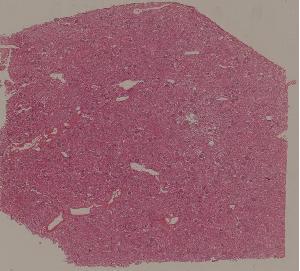

76. Acute pyelonephritis

77. Chronic pyelonephritis

41. Opportunistic infection in the lung

71. Acute transplant rejection of kidney

72. Lupus nephritis

36. Lymphoma

80. Invasive ductal cancer of the breast

84.Graves disease

93. Epidemic cerebrospinal meningitis

94. Encephalitis type B

88. Chronic cavitary tuberculosis of the lung

89. Tuberculous lymphadenitis

90. Lepromatous leprosy of the skin

91. Tuberculoid leprosy

92. Typhoid fever of intestine

95. Poliomyelitis

96. Pulmonary aspergillosis

97. Amebic colitis

98. Schistosomiasis of the colon

99. Experimental acute schistosomiasis of the liver (rabbit)